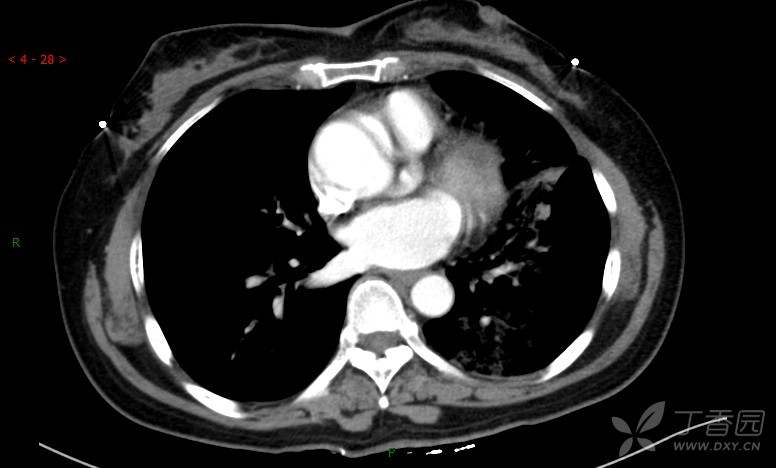

腺泡结节影,蜂窝征,这些都在提示……(病例3连发,附其他2例链接,病理已公布)

原帖名:胸部典型病例3(病例3连发,附其他2例链接)

咳嗽1年余,加重7天。

患者于1年余前始受凉后出现咳嗽,多为干咳,未在意,未到医院就诊。近3月患者出现咳痰,多为黄色粘痰,量大,伴乏力,偶有头晕、心慌,无发热、胸痛、憋喘,无低热、盗汗、咯血、胸痛,无头痛,无恶心、呕吐、腹痛、腹泻,无尿频、尿急、尿痛,在当地诊所给予抗感染等对症支持治疗(具体药物及剂量不详),症状仍时有反复。患者于1月余前到外院就诊,行胸部CT提示双肺炎症,左肺重,考虑为“间质性肺炎”,给予“左氧氟沙星、利巴韦林、头孢哌酮舒巴坦钠注射液”治疗,复查胸部CT示病灶吸收不理想,后出院继续于诊所对症治疗(具体药物及剂量不详),效果欠佳。7天前患者无明显诱因出现上述症状加重,为求进一步诊治,特来我院就诊,我院门诊以“肺炎(重症)?”收入留观室,留观室给予“盐酸莫西沙星氯化钠”等对症治疗后,今日转入我科。患者自发病以来,神志清,精神差,饮食正常,睡眠增多,大小便正常,体重近3月减轻5公斤余。